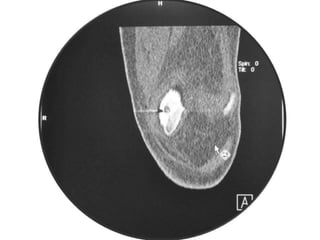

Osteoid Osteoma - CT

• CT is more accurate than MRI.

• CT helped in confirming the diagnosis of

osteoid osteoma in 74% of cases.

• Szendroi et al reported accuracies of about

66% in the diagnosis of intra-articular lesions

and 90% in extra-articular lesions.

• To date, CT scanning is the primary

investigational tool for the definitive diagnosis

of osteoid osteoma.

• A CT guided needle was passed to localize the

lesion.

• Through an anterior "Hernia" approach the

lesion was approached and excised.

• The Follow-up CT Scanning done to reveal

complete removal of lesion.

• A biopsy confirmed it later.